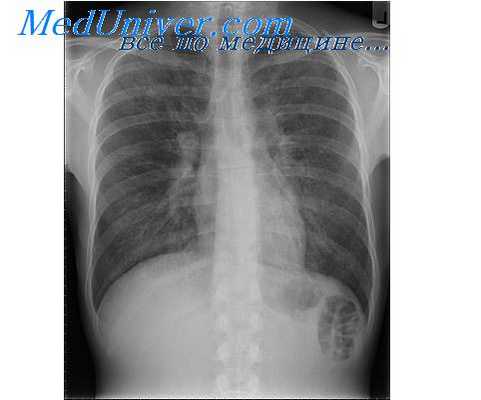

Характеризуя роль нервной системы в развитии воспаления, необходимо остановиться на вопросах сегментарной регуляции воспалительного процесса, а также трофическом влиянии нервной системы на течение воспаления. Данное обстоятельство имеет особое значение при развитии воспалительных заболеваний легких, формировании РДСВ. Показано, что блокирование соответствующих сегментов грудного отдела спинного мозга сопровождается снижением степени выраженности прессорных реакций микрососудов легких и тем самым оптимизацией кислородного обеспечения легочной ткани, снижением концентрации метаболитов, усиливающих деструктивные процессы.